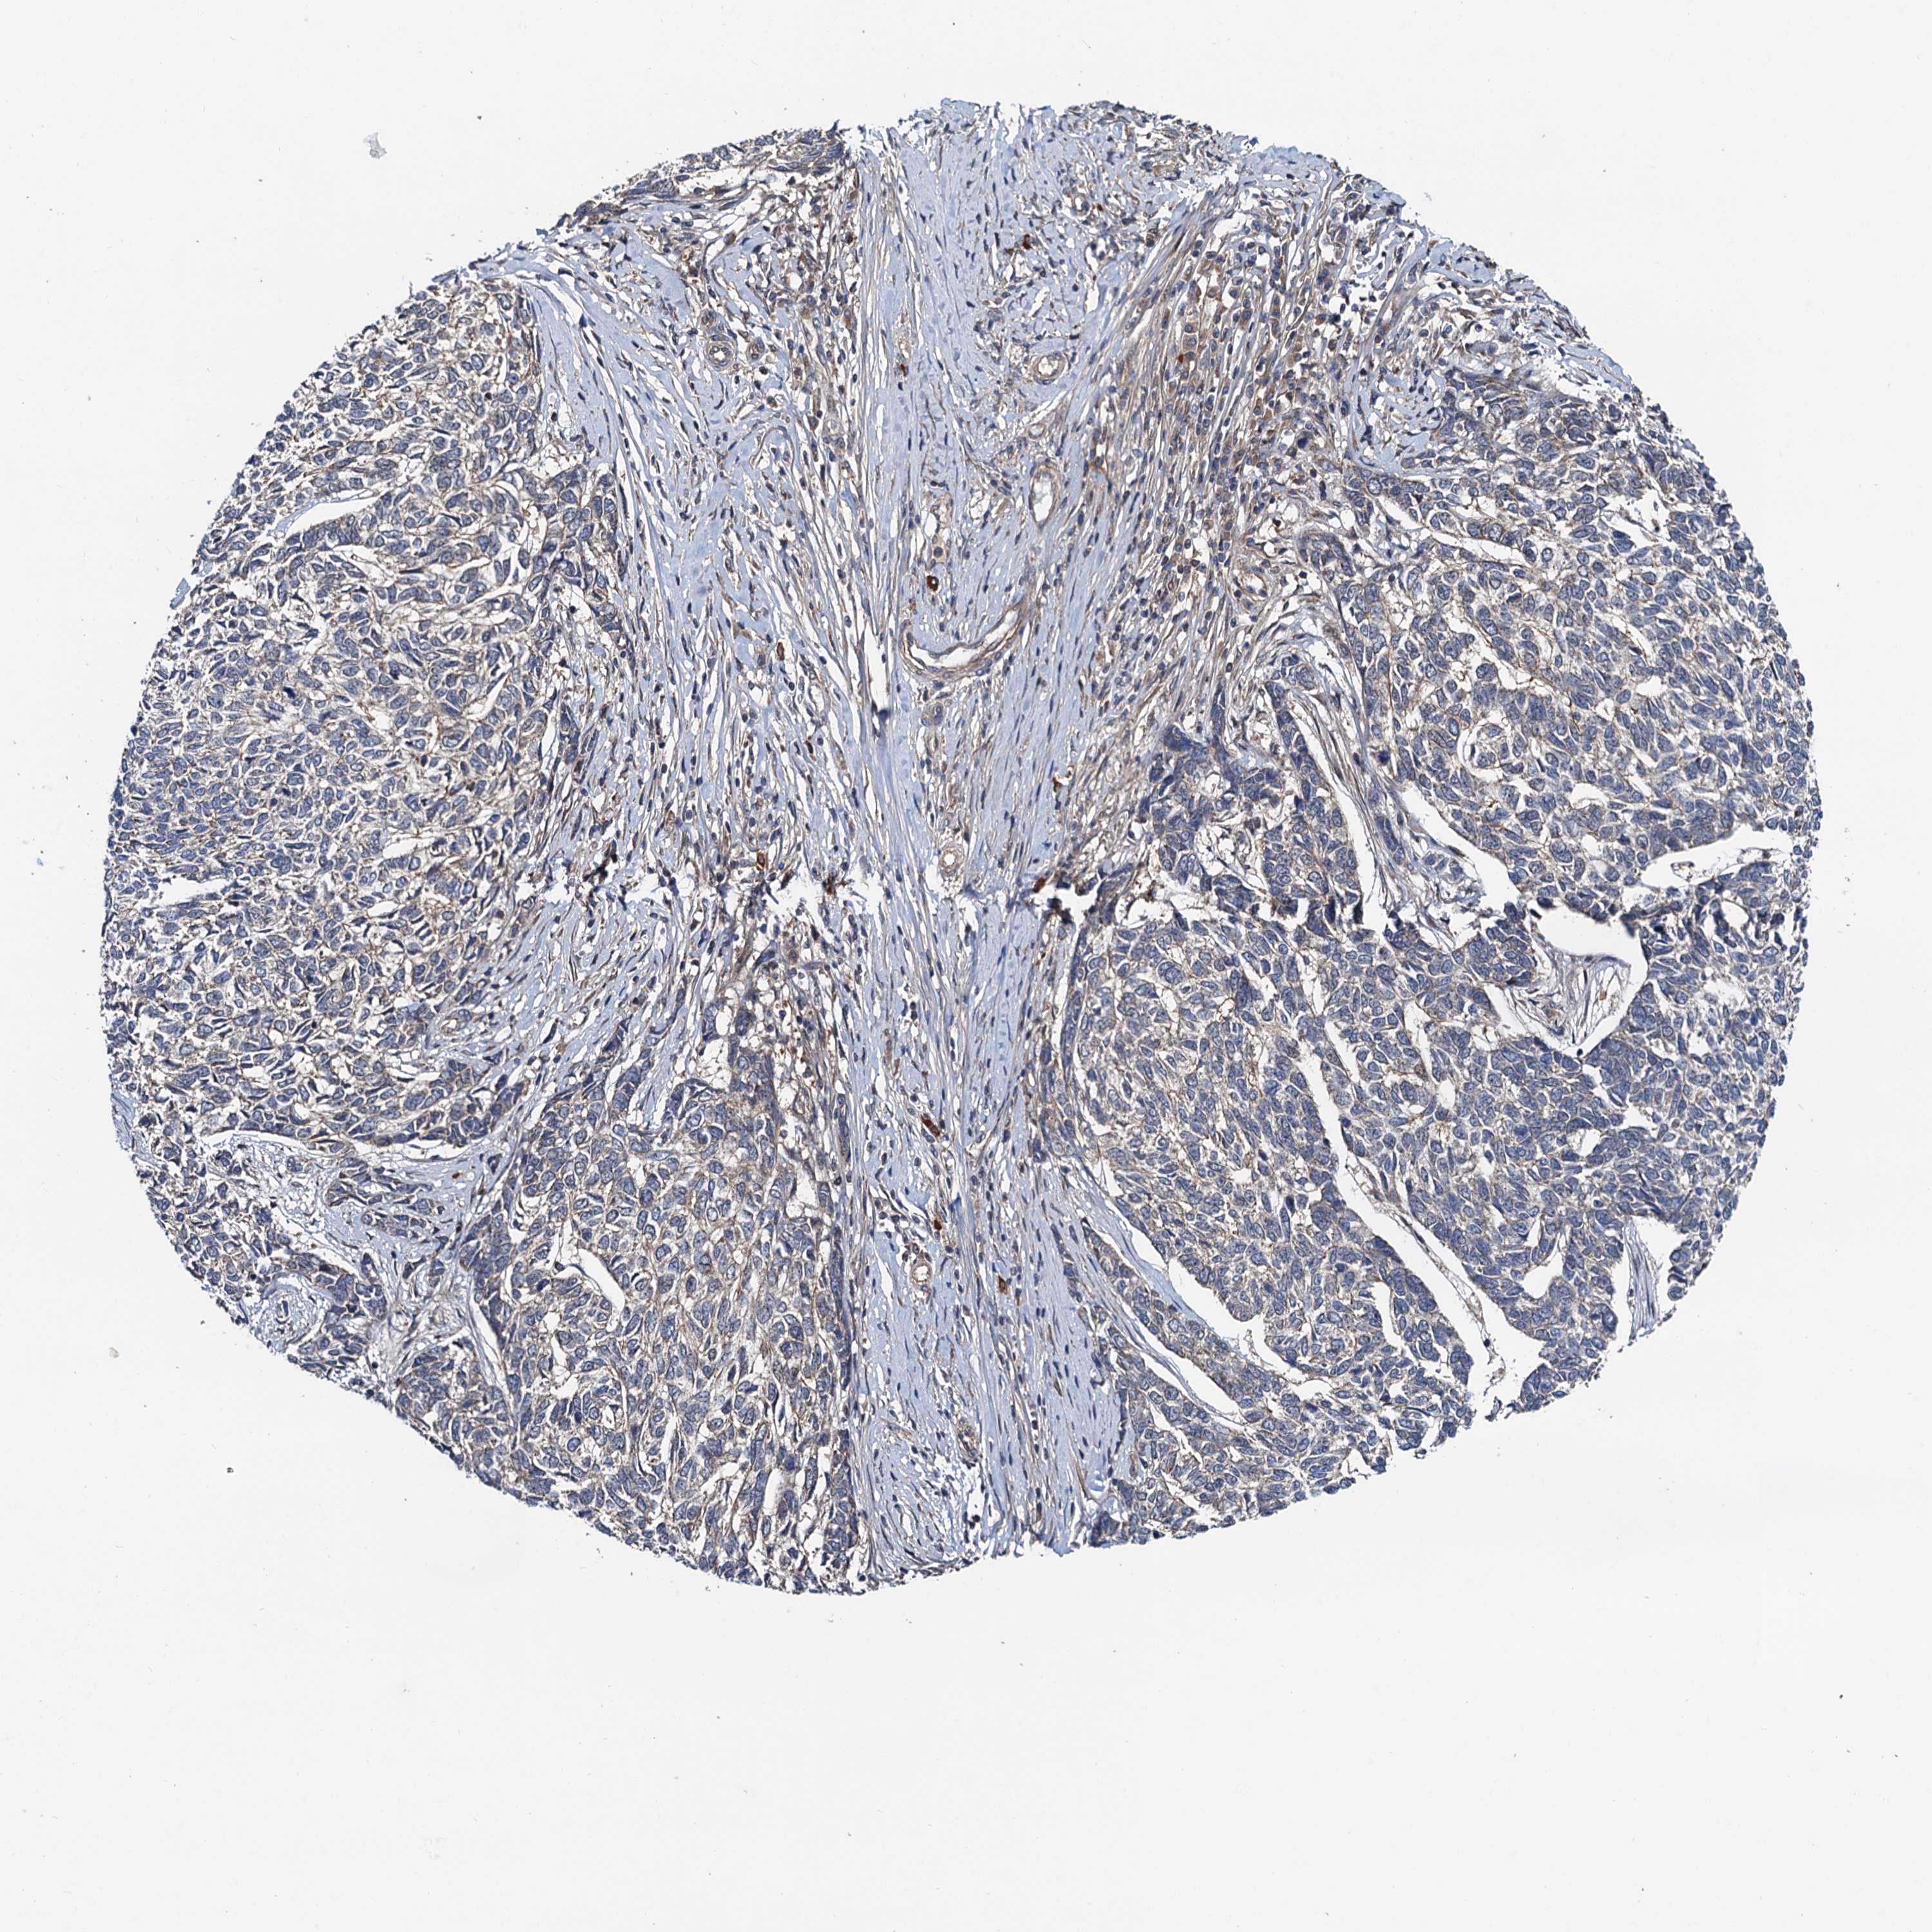

Basal cell and squamous cell cancer

SKIN CANCER - Protein expressioni

A mouse-over function shows sample information and annotation data. Click on an image to view it in a full screen mode. Samples can be filtered based on level of antibody staining by selecting one or several of the following categories: high, medium, low and not detected. The assay and annotation is described here.

Antibody stainingi

Antibody staining in the annotated cell types in the current human tissue is reported as not detected, low, medium, or high, based on conventional immunohistochemistry profiling in selected tissues. This score is based on the combination of the staining intensity and fraction of stained cells.

Each image is clickable and will lead to virtual microscopy that enables deeper exploration of all samples and also displays staining intensity scores, fraction scores and subcellular localization as well as patient and tissue information for each sample.

Antibody HPA039371

Antibody HPA040174

Staining

High

Medium

Low

Not detected

Intensity

Strong

Moderate

Weak

Negative

Quantity

>75%

75%-25%

<25%

None

Location

Nuclear

Cytoplasmic/membranous

Cytoplasmic/membranous,nuclear

Basal cell carcinoma

Squamous cell carcinoma, NOS

Squamous cell carcinoma, metastatic, NOS